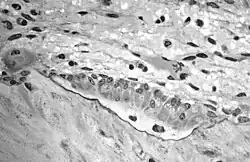

Остеобла́сты (от др.-греч. ὀστέον — «кость» + др.-греч. βλάστη — «росток, отпрыск, побег») — молодые клетки костной ткани (диаметром 15-20 мкм), которые синтезируют межклеточное вещество — матрикс. По мере накопления межклеточного вещества остеобласты замуровываются в нём и становятся остеоцитами. Остеобласты богаты элементами зернистой эндоплазматической сети, рибосомами, имеют хорошо развитый комплекс Гольджи. Их многочисленные отростки контактируют между собой и с отростками остеоцитов. Вспомогательной функцией остеобластов является участие в процессе отложения солей кальция в межклеточном веществе (кальцификации матрикса) благодаря высокому содержанию щелочной фосфатазы, что свидетельствует о высокой синтетической активности остеобластов. При этом происходит образование полостей (лакун), в которых они и залегают, превращаясь в остеоциты.

Остеобласты возникают из мезенхимальных стволовых клеток[1]. По форме остеобласты делятся на три группы: кубические, пирамидальные и угловатые (многоугольные).

В сформировавшейся кости остеобласты встречаются только в местах разрушения и восстановления костной ткани, тогда как в развивающейся кости они непрерывным слоем покрывают почти всю поверхность формирующейся костной балки. Остеобласты располагаются вокруг первичных костных перекладин, образованных коллагеновыми волокнами. Оказавшись между ними, многие остеобласты замуровываются в межклеточном веществе и становятся остеоцитами. Так возникает костная ткань.